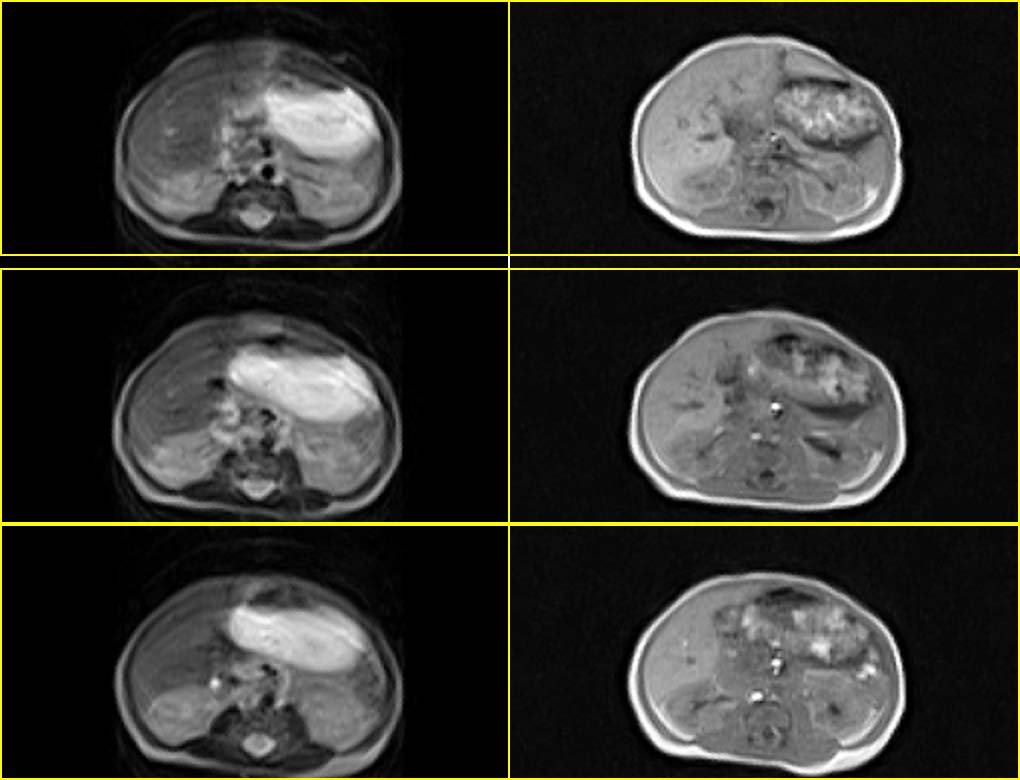

患者男性,3天.

因生育前b超发现肝脏占位,怀疑血管瘤而行mr检查.

血管内皮瘤,建议补充临床资料,如血常规,尤其血小板情况,有无充血性心衰,主要与肝母鉴别.

考虑肝母